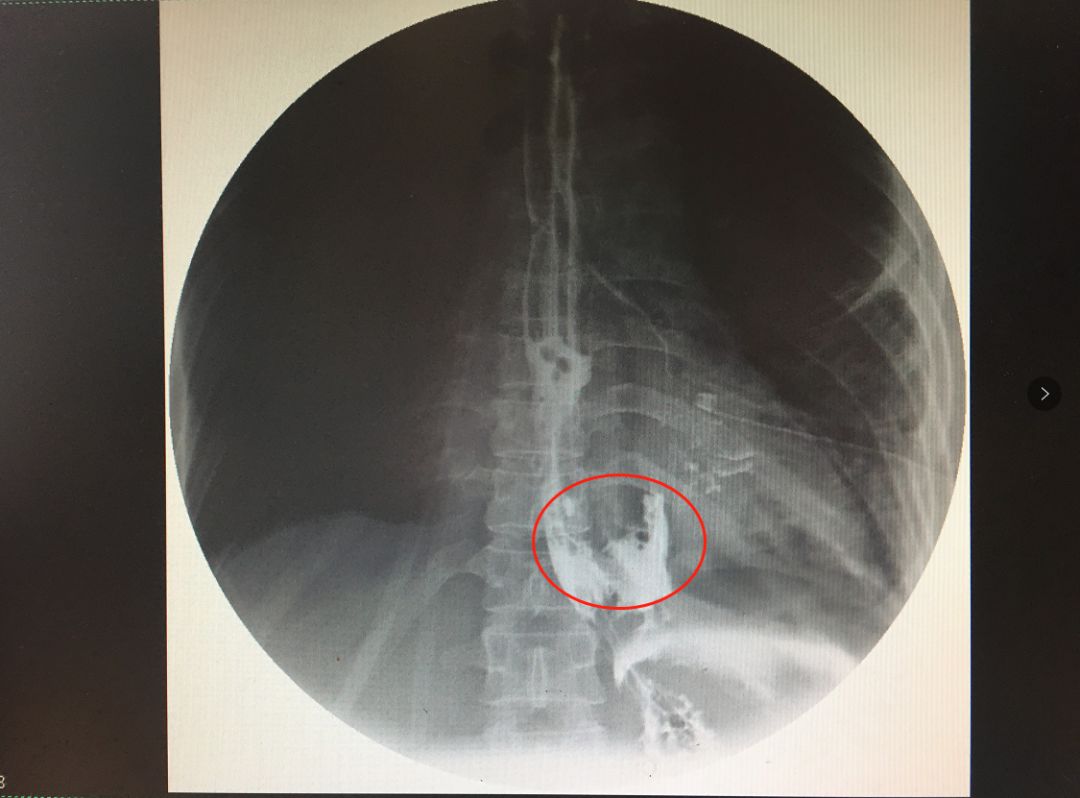

福州一男子突发腹痛险些丧命,原因竟是食管破裂!